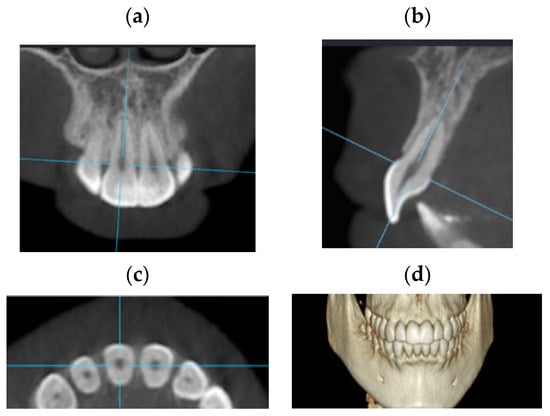

2.2. Radiographic Technique

2.3. CBCT Technique

2.4. Radiological Assessment